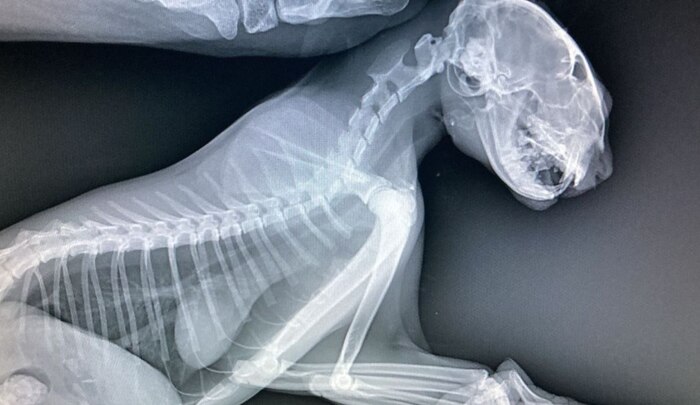

Всем привет! У меня есть кот, подобрал пару лет назад, сбитого, на обочине, без сознания. Сначала он был совсем не очень живым, но после двух недель в стационаре вроде поправился(немного шокирован был от того сколько стоит лечение). После того, как забрал домой, кот понятное дело долго приходил в себя, ходил не очень уверенно, не очень понимал что происходит. Периодически были видны последствия черепно-мозговой травмы(невозможность сконцентрироваться на одном объекте, я так понял, т.к он постоянно провожал взглядом непонятно что с одной стороны в другую и так по кругу(хз как по другому объяснить). Потом окреп и стал более уверенным, есть еще кошка и кот, с котом подружился, с кошкой до сих пор нет. Так вот проблема в том, что после того как он более менее пришел в себя - начал ходить по квартире и просто кричать, сначала было терпимо, потом невыносимо. Купил успокоительные в вет. аптеке - вроде сначала успокаивали, потом какие то нервные срывы бесконтрольные начались, перестали давать таблетки. Прошло какое то время и он стал обычным ленивым котом. Но пару месяцев назад он опять начал ходить из угла в угол и орать, мы уже привыкли, но хочется это изменить, он может несколько часов подряд ходить и кричать, потом дышит как пес, отдохнет 10-20 мин и опять ходит. Если знаете, что делать или к какому конкретно врачу обратиться - подскажите пожалуйста. Учитывая невозможность проверить чисты ли на руку вет. клиники, хотелось бы сразу попасть к нужному специалисту, а не выкинуть много денег на обычные - «У вас отличный кот, спасибо, что показали». Спасибо. Плюсаните пожалуйста, хочется, чтобы Олег перестал переживать)